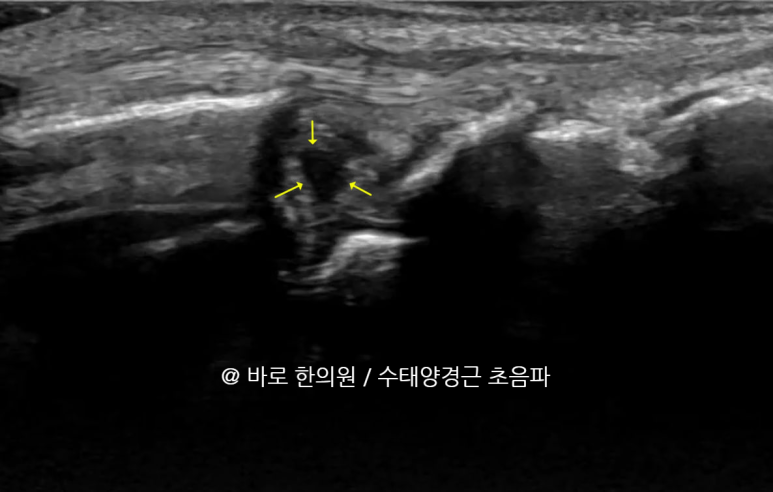

MRI상 삼각섬유연골 파열로

진단 받으신 분들은

표준 경혈 초음파와 달리이렇게까맣게 손상된 틈이 보이는데요.

제가 1억이 넘는 GE초음파 최상위 기종

LOGIQ FORTIS를 쓰고 있는데

사람에 따라서

요골 부착부나 척골 부착부쪽은

안 보일 때가 있습니다.

양방 초음파든 한방 초음파든

삼각섬유연골의 전체 범위를 볼 수 없어서

확실하게 진단할 순 없고요.

반드시 MRI를 찍어봐야 합니다.